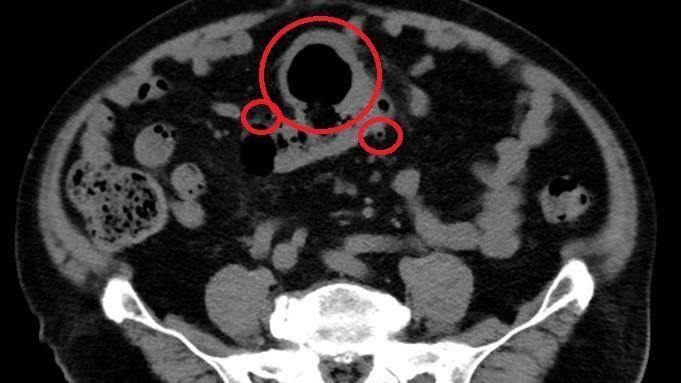

▲電腦斷層影像可見大腸有多處憩室。(圖/台北慈濟醫院提供)

大腸直腸外科醫師陳信宏從電腦斷層發現趙先生的大腸有多處憩室,合併乙狀結腸巨大囊狀腫塊,已產生腹水,其中最大的憩室有7、8公分。所幸經切片化驗排除惡性腫瘤,醫療團隊以微創腹腔鏡手術切除乙狀結腸,5天後趙先生平安出院。